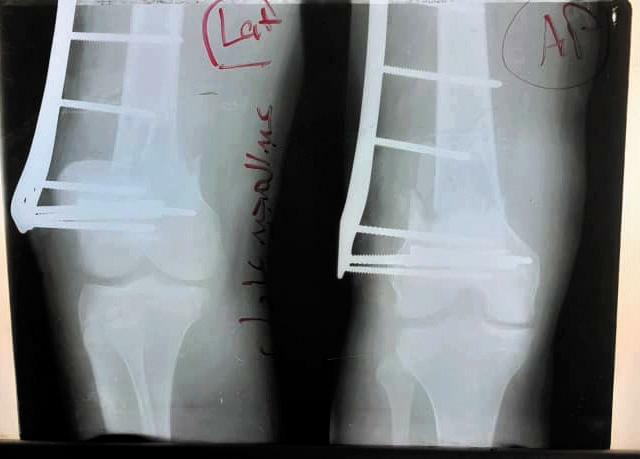

开放骨折最常见的原因是车祸,尤其是在交通工具相对落后、安全系数较差的苏丹,车祸致开放骨折患者非常多;最重要的是医疗设备落后及医疗环境差导致开放骨折致残率和截肢率极高。7月20日,余国勇大夫救治一严重开放骨折患者,入院时已13小时,出血多,患者已几乎处于休克状态,需抢救及行急诊手术,但要行手术需克服重重困难:1.受伤已超过6-8小时,伤口感染的风险极高;2.需输血,但血液需从首都送,最少需要4小时;3.无准备的骨折固定器械等。这里医疗条件落后,以往类似的患者都进行截肢了,但患者年轻,保全肢对患者来说极为重要,余国勇医生坚持克服种种困难为患者进行了保肢手术。经积极抢救,急诊手术顺利,患者生命体征平稳。

随后余国勇医生克服各种困难又为患者进行了两次手术,为患者得到了成功的救治并保全了肢体,此类手术的成功开展给当地患者的带来了福音,也扩大了中国医疗队的影响力。中国医疗队不远万里来到非洲苏丹这片热土上,用青春和汗水不断的去诠释和贯穿“不畏艰苦,甘于奉献,救死扶伤,大爱无疆”援外医疗精神。